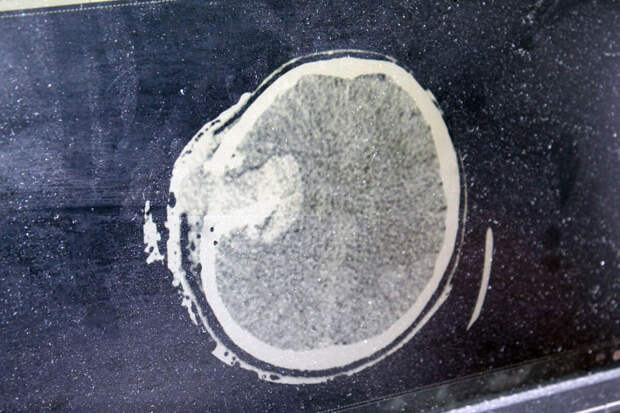

У мужчины диагностировали открытую проникающую черепно-мозговую травму, ушиб головного мозга тяжелой степени с внутримозговой гематомой и кровоизлиянием в вещество мозга. Требовалась срочная операция по удалению гематомы - трепанация черепа. По словам, врача-нейрохирурга Сергея Сергеева, промедление грозило бы летальным исходом, операция шла более трех часов. Пациента ввели в медикаментозную кому, в которой он находился более 10 дней.